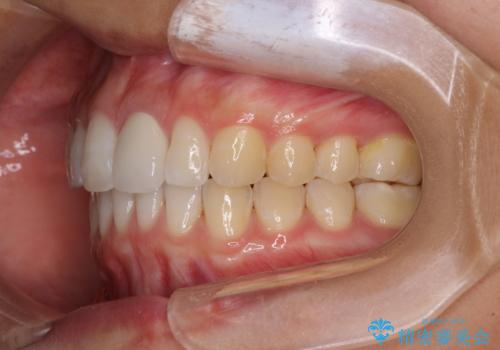

前歯を整えたい 小さい前歯がある 矯正・セラミック併用で美しく インビザラインでも抜歯矯正できます

総合歯科治療 矯正治療と失活歯のセラミック補綴治療

欠損歯と矮小歯 矯正治療と前歯のセラミック治療